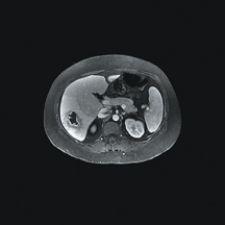

The next phase of MRI lays in identifying metastasis in the abdomen. The greatest challenge for abdominal MR exams is that one in 10 are rendered inconclusive due to motion artifacts or inadequate resolution. To remedy this problem, GE Healthcare has integrated its MR systems Signa HD 1.5T and Signa HD 3.0T with a new MRI software called LAVA (liver acquisition with volume acceleration). LAVA combines contrast-enhanced, multiphasic imaging with fat suppression for MR liver imaging. The MR system can scan the entire liver of a large patient in a single breath-hold, which is particularly helpful with patients who have difficulty holding their breath, and LAVA reportedly achieves 25 percent more resolution with 25 percent more coverage compared to other standard MR devices.